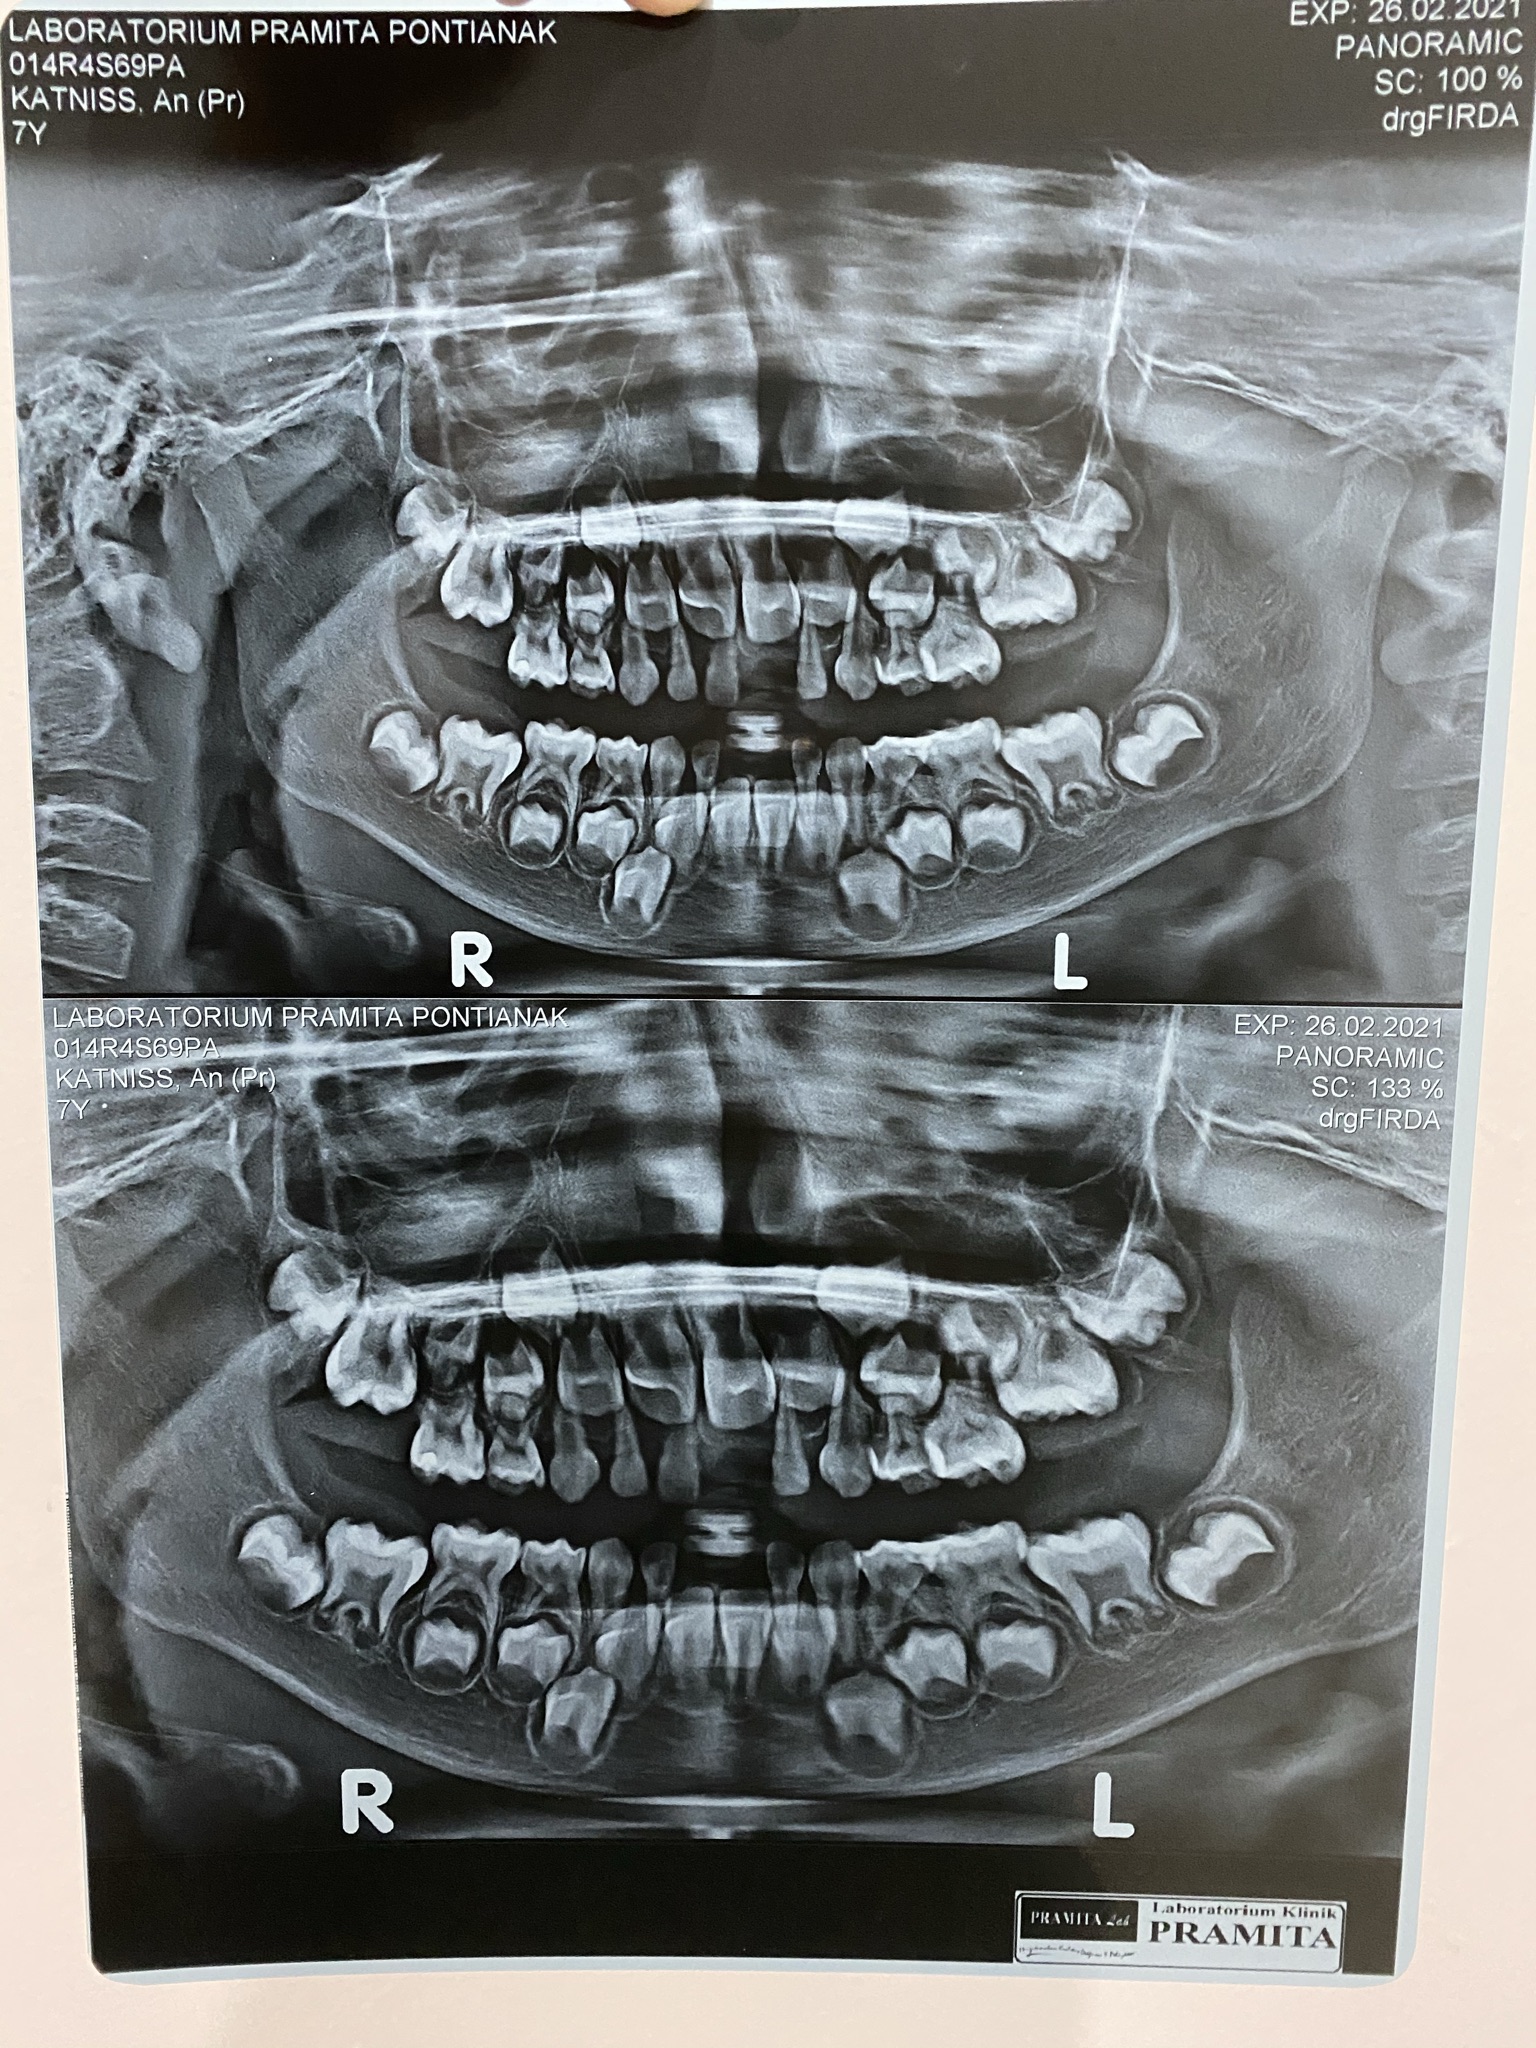

Setelah giginya dicabut, dokter giginya menyarankan untuk rontgen mulutnya. Mau lihat bagaimana perkembangan bakal-bakal gigi permanennya nanti. Kita ya ikut aja karena penasaran juga dengan gigi dia di masa yang akan datang. Dan ini dia hasilnya.

Menurut dokter giginya seh seluruh calon gigi permanen si K sudah ada dan siap untuk tumbuh ke atas menggantikan gigi susunya. Emaknya pun akhirnya lega. Akan tetapi, emang bisa semulus itu selesainya? Ya tentu tidak dong! Hahahahaha.